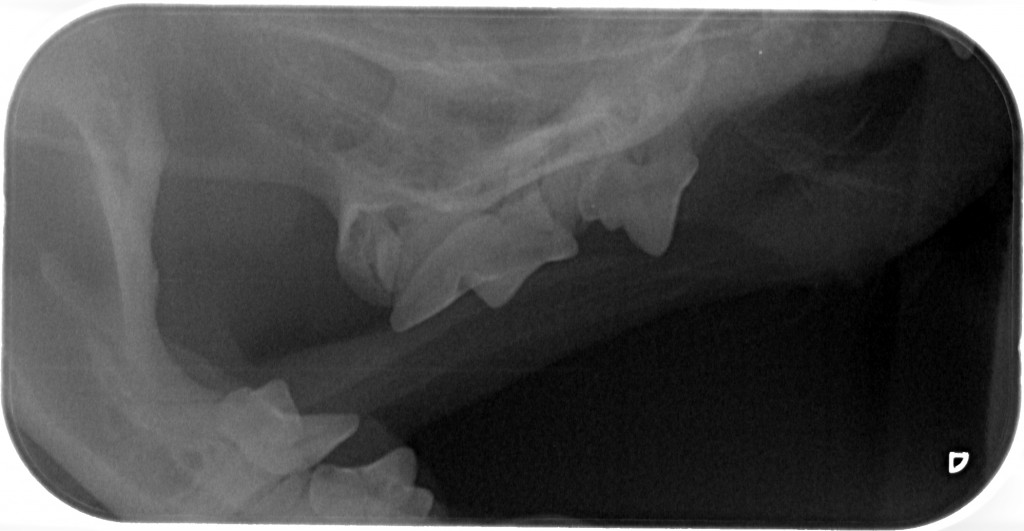

www.kattensliv.dk_Sygdomme hos katte fra P-T_Tænder_Mundproblemer_Shana-Mio_6

Fuld størrelse er

1024 × 531